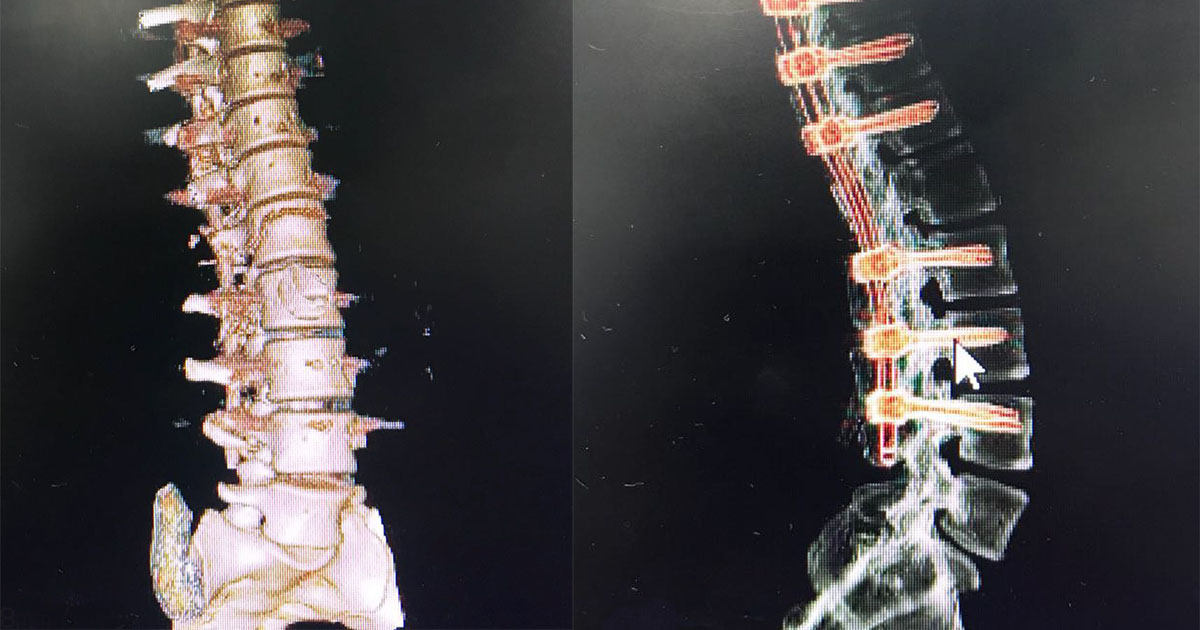

Una vez establecido el caso, se realizó junta médica para determinar el plan y los pasos a seguir. Por ello, la especialidad de neurocirugía indicó una estabilización de unión toracolumbar con fijación transpendicular con fines ortopédicos y reducción de luxofractura por medio de una artrodesis.

Ante la gravedad del hecho se realizó la cirugía sin ningún tipo de complicación en el estado de salud de la paciente, teniendo como resultado una notoria mejoría al estabilizar vertebras y médula espinal dentro del eje central de la columna. Dicho caso se suma a los procedimientos de alta complejidad que se realizan en Clínica Medical. Una vez más se confirma que es una institución líder a nivel local y nacional en la atención de pacientes con trauma.